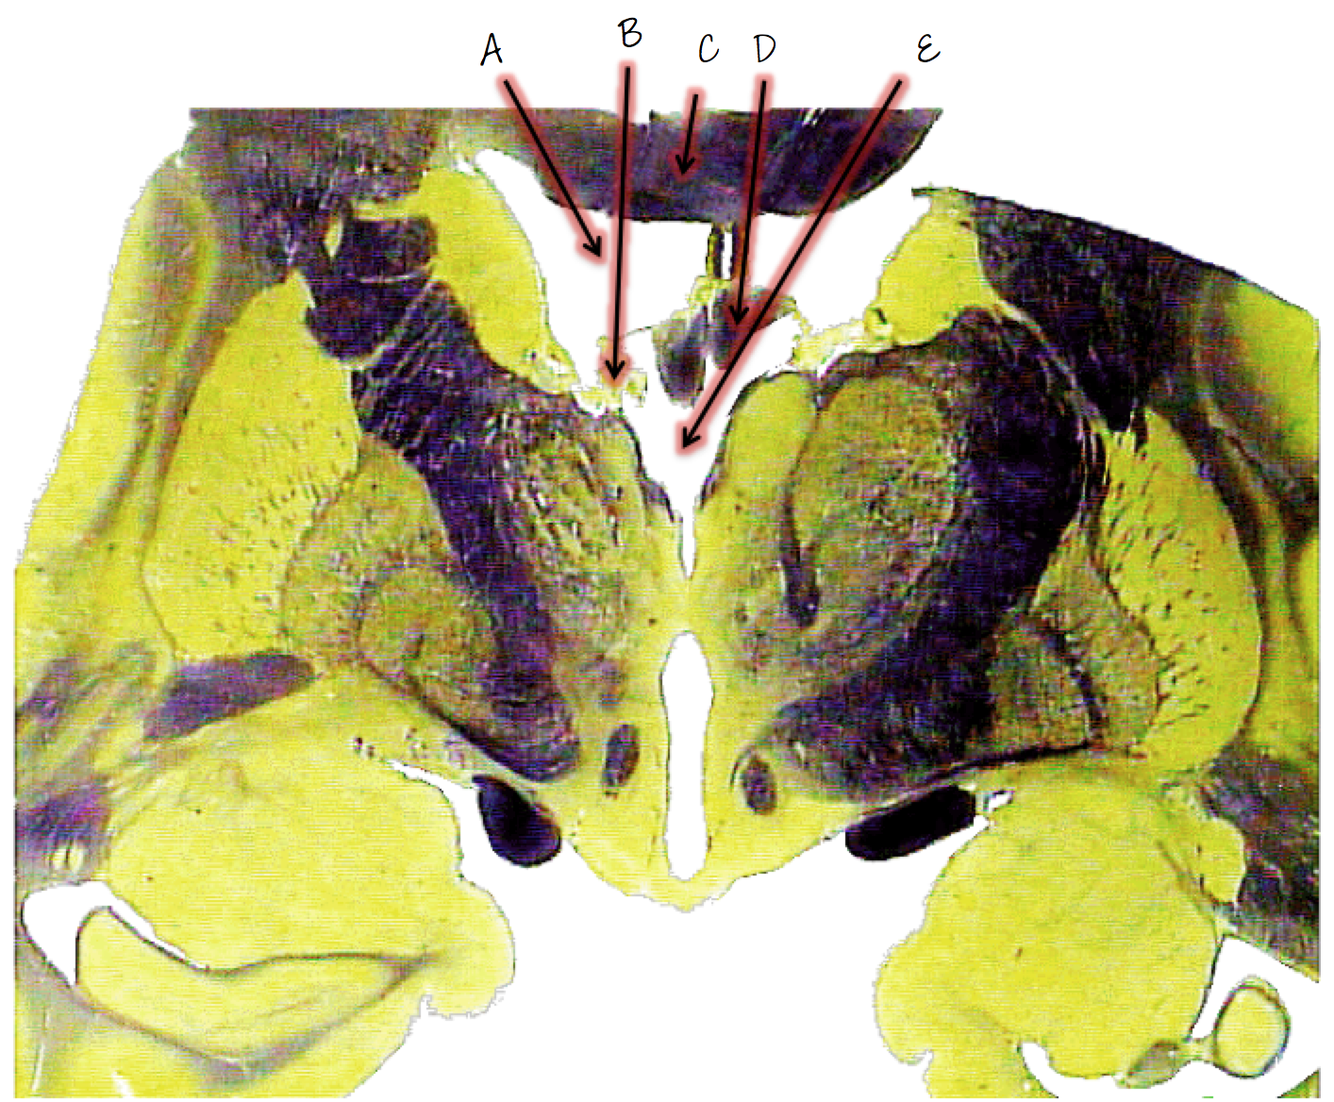

A; lateral ventricle

B; choroid plexus

C; corpus callosum

D; fornix

E; third ventricle